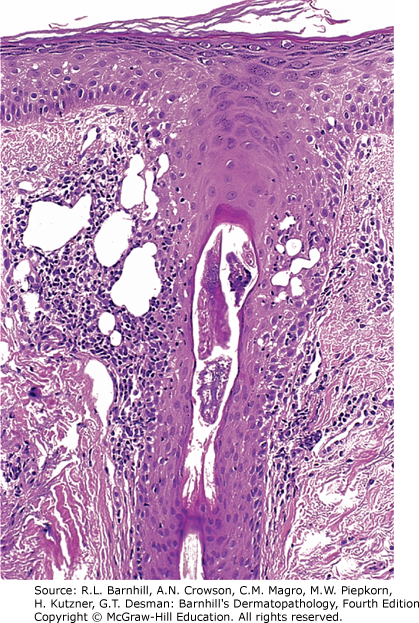

Pictured above within the hair follicle is a Demodex mite. Demodex's involvement in acne rosacea is controversial but many believe an overgrowth of Demodex and the subsequent inflammatory reaction to the mite can contribute to the pustular eruption. Resolution of facial rash with medications such as ivermectin or permethrin is further evidence of their involvement in certain types of rosacea. Histologically, follicular spongiosis and adjacent lymphohistiocytic infiltrate are suggestive of an inflammatory response to the Demodex mite. Another example of a Demodex mite within the hair follicle is shown below.